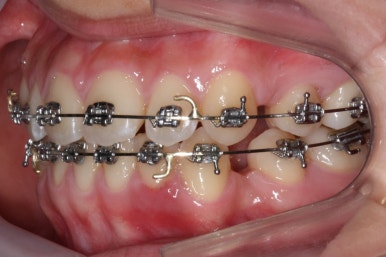

장치를 부착하였습니다.

부산교정전문의 키다리아저씨치과에서 이번에 사용한 장치는 메탈장치이며, 가장 기본적이고 역사가 오래된 장치가 되겠습니다.

발치교정이라고 하더라도 처음부터 바로 이를 뽑을 때도 있고, 몇 달 후에 뽑을 때도 있습니다.

뽑힐 치아라 하더라도 다른 치아를 가지런히하는데 최대한 이용해주고, 교정장치를 붙이고 좀 움직인 상태에서 발치를 하게되면 통증이나 불편감 없이 굉장히 수월하게 발치를 할 수 있기 때문입니다.